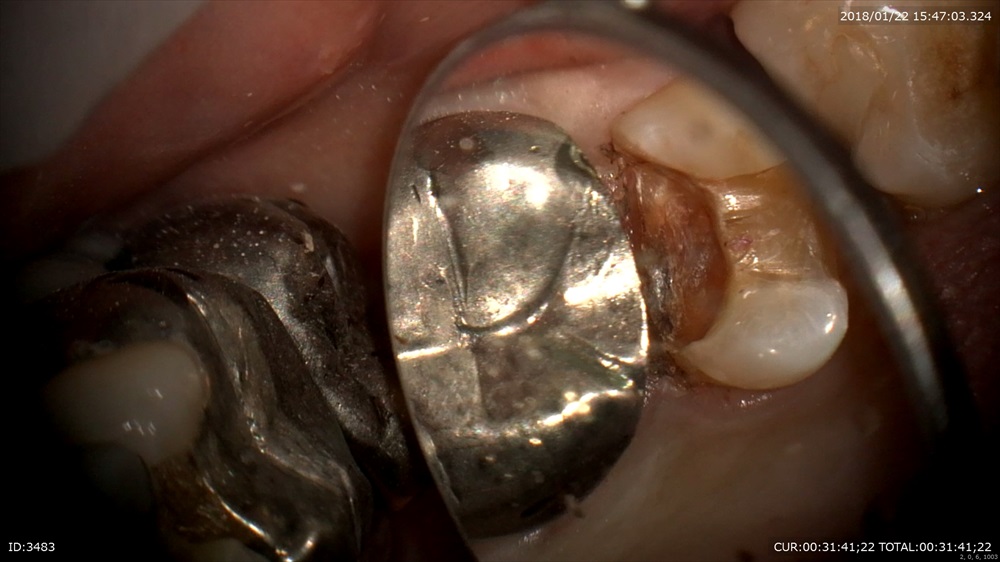

次はむし歯

銀歯むし歯の恐ろしさ。。。

銀歯が取れたで来院。歯科ドックで歯茎の中までむし歯と診断しました。

丁寧に。深い。歯茎の中まで。銀歯の恐ろしさ。。

ここで電気メス!(無痛)

こんな器具があると無痛で止血と形成が可能です。

コンポジットでビルドアップ

これで精密な型をとります。患者さまにもこの画像をしっかり説明!安心の治療。